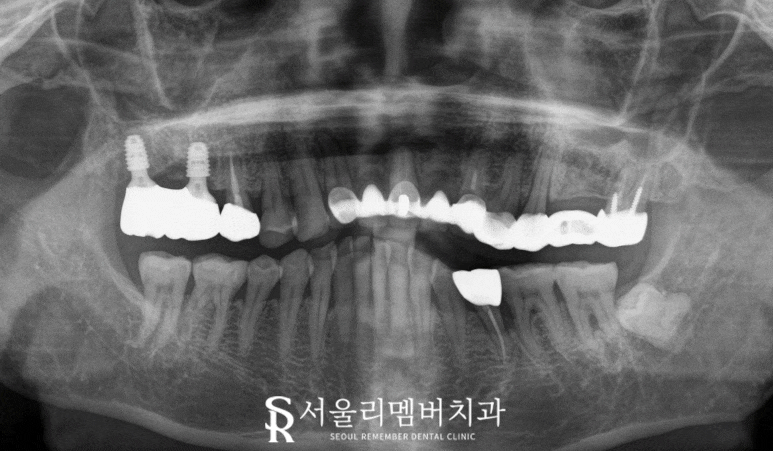

서울대입구역 치과 에서는

구강 내 나타난 증상에 따라

어떤 진료가 좋을지

정확한 진단을 위해

파노라마 엑스레이를 찍게 되는데요,

이 과정까지 거쳐야

비로소 여러 임상검사와

엑스레이 사진,

그리고 환자가 호소하는 동통에 따른

진단을 세울 수 있습니다.

2024.07.11

2024.12.03

problem & solution

① 오른쪽 위 어금니

치조골 소실 및 이차우식

-> 발치 후 임플란트

② 크랙 의심 치아

-> 신경치료 크라운

③ 교합면 우식

-> 인레이